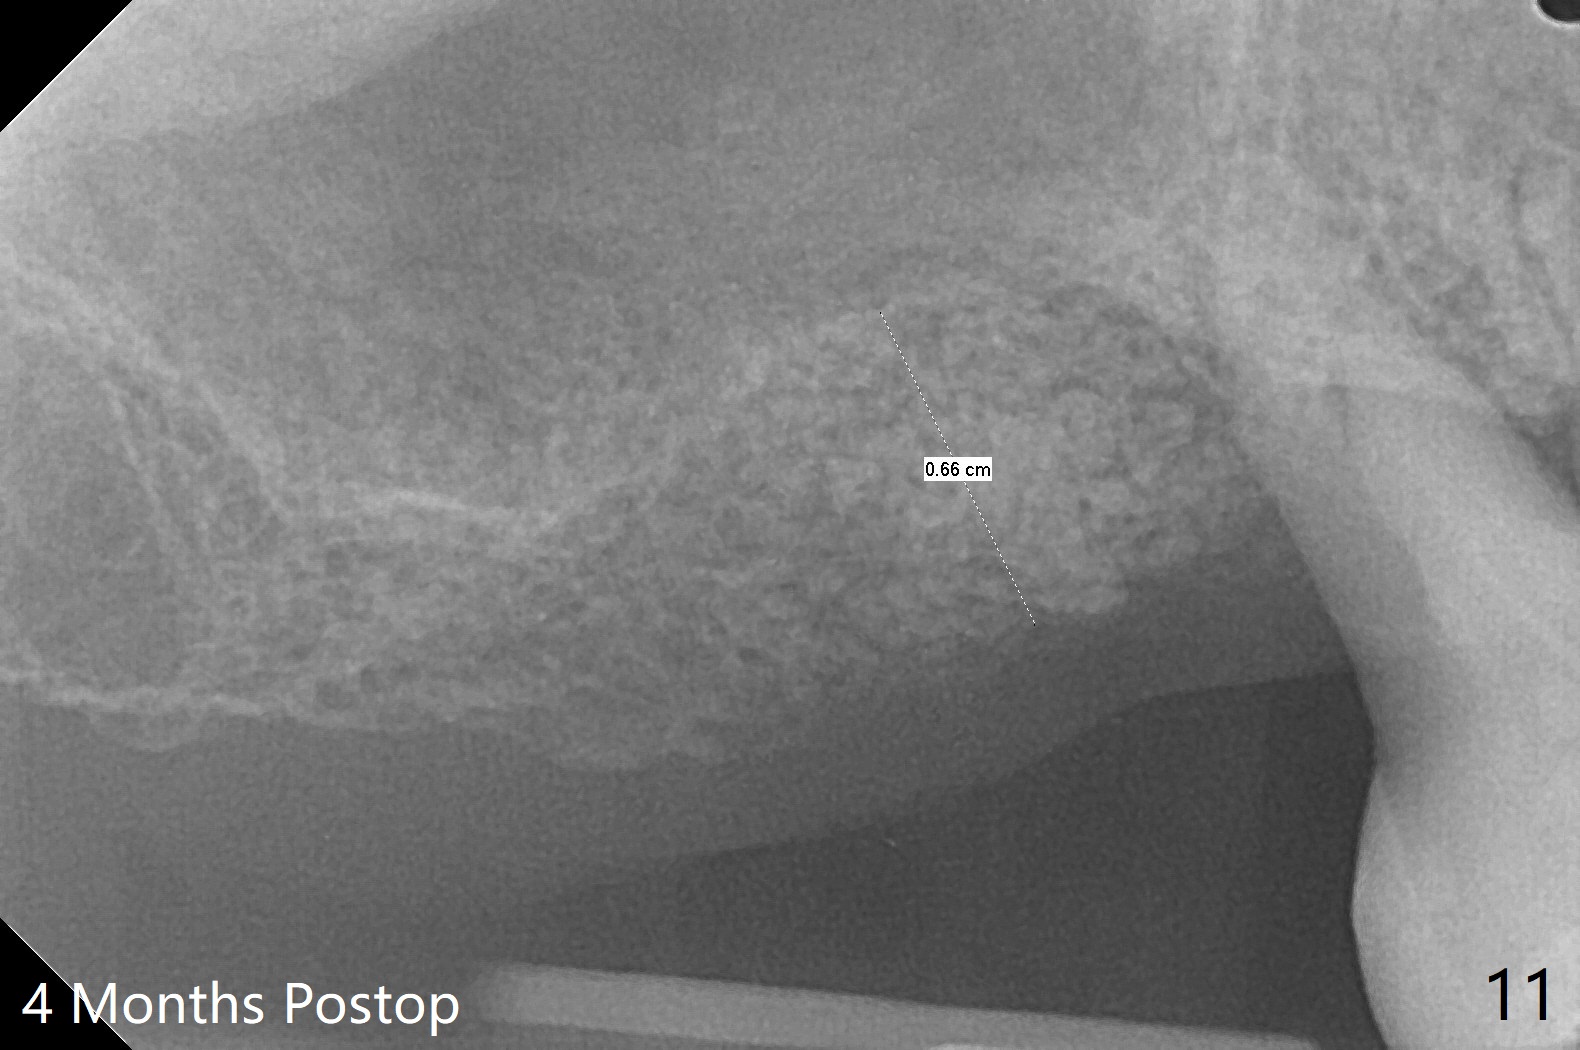

尽管右上第一,二磨牙骨质吸收严重,为了保持牙乳头,先拔除有症状第二磨牙,但是后者牙槽窝与第一磨牙之间好像没有软组织(图二:*),所以骨粉(图一,二:7)无法从前者推入后者(图二(下一个成功病例))。骨粉表面放置6个月吸收膜(GEM Cap(图三::C)),使用牙周胶水固定,而且装置牙齿空间维持器(图二:S)和牙周敷料强化固位。牙齿拔除证实腭侧牙槽窝(图四:P)上颌窦底板穿孔(^;但是没有漏气)。虽然病人已经服用Amoxicillin一周以及Z Pack(两颗,术前),为了防止感染介入上颌窦,穿孔冠部放置胶原塞(图五:黄色),然后放置骨粉(红色)。后者仿佛增加骨质高度不少(图二)。如果不够,以后再做提升。多亏间隙保持器,牙周敷料术后4天没有松动迹象(图六)。术后三周敷料颊侧有些破裂(图七),而舌侧完整(图八)。嘱咐病人正常刷牙和水牙线,让敷料自行脱落。其实术后六周敷料仍在原位,不可吸收膜粘附于敷料,两者一起去除,伤口愈合(图九),骨粉好像没有损失(图十)骨高度减少。术后4个月骨质高度继续减少(图十一)。植骨后骨质高度还与邻牙一致,密度低,可植入5x7.3毫米植体(图十二)。